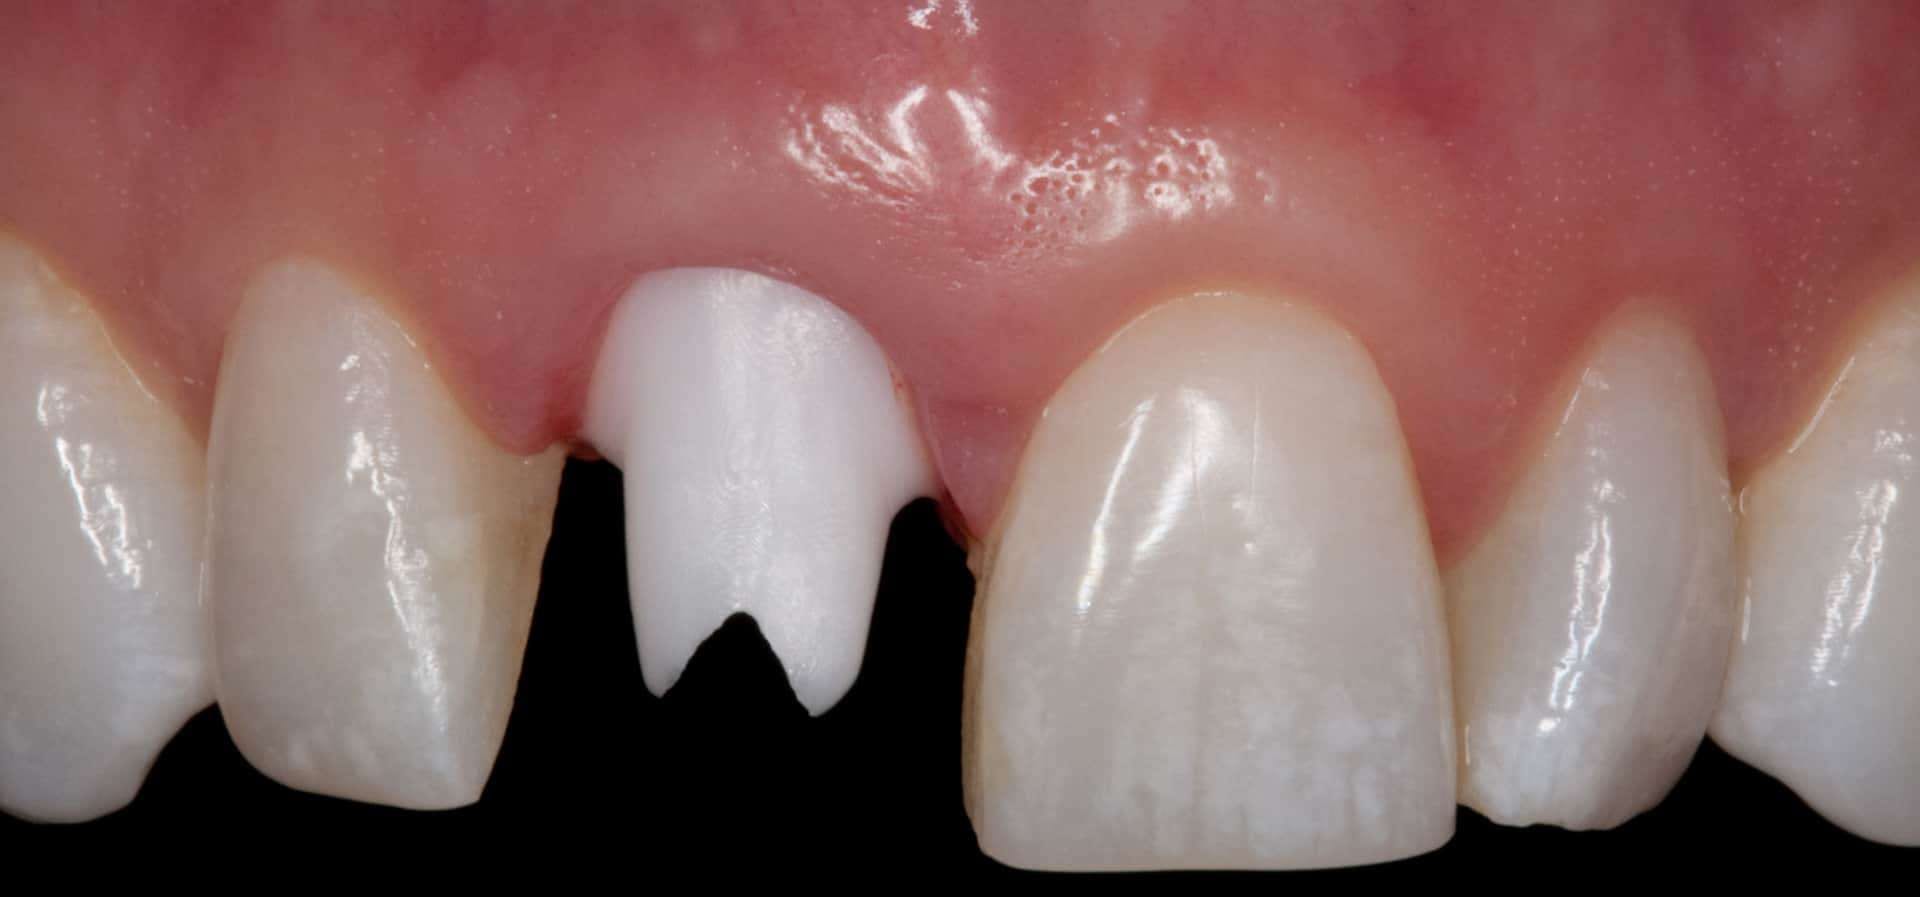

Before:Â Fractured/failed heavily treated upper right central incisor (tooth #8). The root is non-restorable and requires removal. The treatment of choice is a single implant supported restoration.